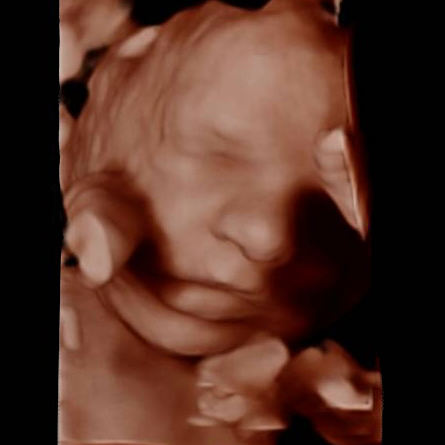

2d, 3d,4d & HD live

Enjoy a private, affordable ultrasound from the comfort of your home, perfect for moms between 7–41 weeks. Share the moment with loved ones by connecting directly to your TV for real-time viewing in 2D, 3D, or 4D. Ideal for baby showers or gender reveal parties!